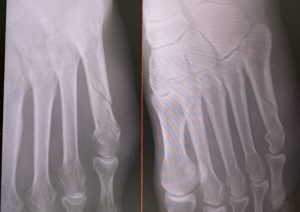

ズレの確認の為もあってか、毎週レントゲンを撮っています。

画像を見ると、うっすらですが折れている骨のあたりが白く形成されてきているのがわかります。